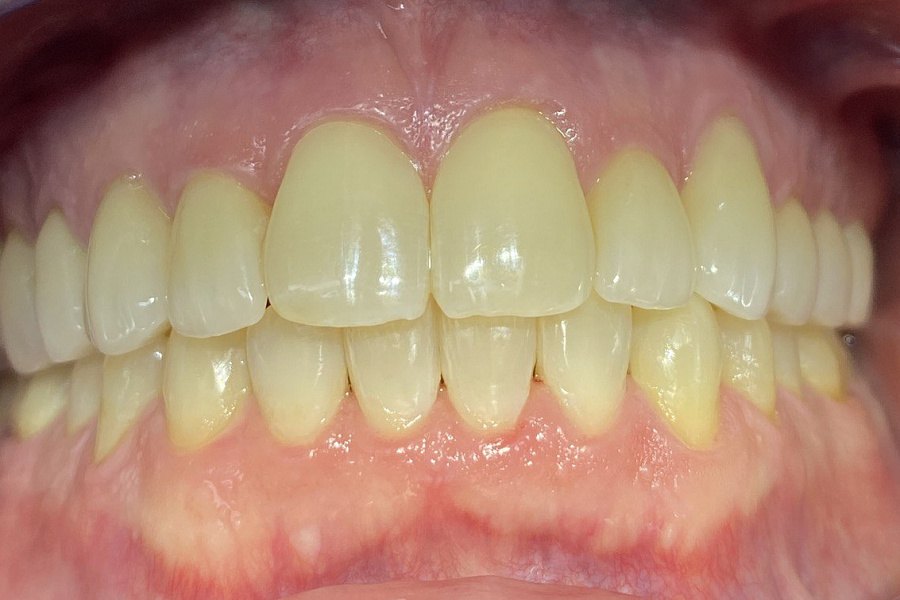

Этапы лечения

1. санация полости рта

2. ортодонтическое лечение с помощью элайнеров

3. восстановление плотных межзубных контактов с помощью ортопедических конструкций

4. виниры 12, 22 для удлинения резцов.

Ортодонтическое лечение с помощью элайнеров длилось 10 месяцев. Далее последовало протезирование и установка виниров.